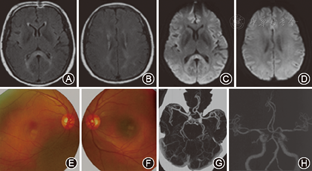

4例患者分别于发病后第1、第15、第1、第3天行MRI检查。3例MRI表现为胼胝体压部中心区孤立的类圆形病变,病变在T1WI上呈等或低信号,T2WI上呈高或稍高信号,FLAIR及DWI为高信号(图1)。1例表现为整个胼胝体压部弧形病变,同时累及双侧半卵圆中心、侧脑室旁及皮质下白质,病变在T1WI呈等信号,T2WI、FLAIR呈高信号,DWI仅可见胼胝体压部弧形高信号(图2)。

MRI显示胼胝体压部的孤立性异常信号和病灶的可逆性消失是本病主要的诊断依据。Takanashi等[7,8]根据MRI特点将MRES其分为Ⅰ型和Ⅱ型,即病灶局限于胼胝体压部的Ⅰ型和同时累及深部白质或皮质下白质的Ⅱ。本组3例患者MRI表现为胼胝体压部的孤立的类圆形病变,符合MRES分型Ⅰ型;1例表现为整个胼胝体压部受累的弧形病变,类似于"回旋镖征"[9],同时累及胼胝体外,符合Ⅱ型。Takanashi等[7]发现MRES Ⅱ型可向Ⅰ型转变,胼胝体外的异常信号可先于胼胝体压部的异常信号消失。本组1例患者MRI上DWI仅见胼胝体压部异常信号,而T2WI、FLAIR显示胼胝体及胼胝体外异常信号,推测这种不匹配的其可能的原因是患者行MRI检查是处于Ⅱ型向Ⅰ型转换的中间阶段,胼胝体外病变正逐渐消失,DWI较T2WI及FLAIR能够更敏感的显示这种改变。本研究Ⅰ型和Ⅱ型患者的临床症状及预后方面无差异,与Takanashi等[8]的报道一致。也有研究发现,胼胝体外病变的出现可能提示预后不良[10]。本组4例患者MRI病变在首次行MRI检查后4~17 d消失,患者临床症状的完全恢复晚于MRI病灶的消失。